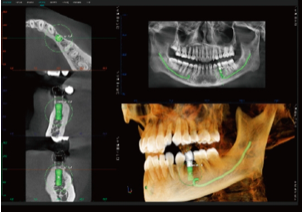

Planeamento Virtual de Implantes

Permite a simulação de procedimentos de implantes (implante + pilar + coroa), ajudando a selecionar o implante mais adequado.

Fornece alertas de proximidade ao canal nervoso, aumentando a segurança cirúrgica.

Facilita a comunicação entre médico e paciente, permitindo ao paciente visualizar claramente o procedimento de implante planeado.